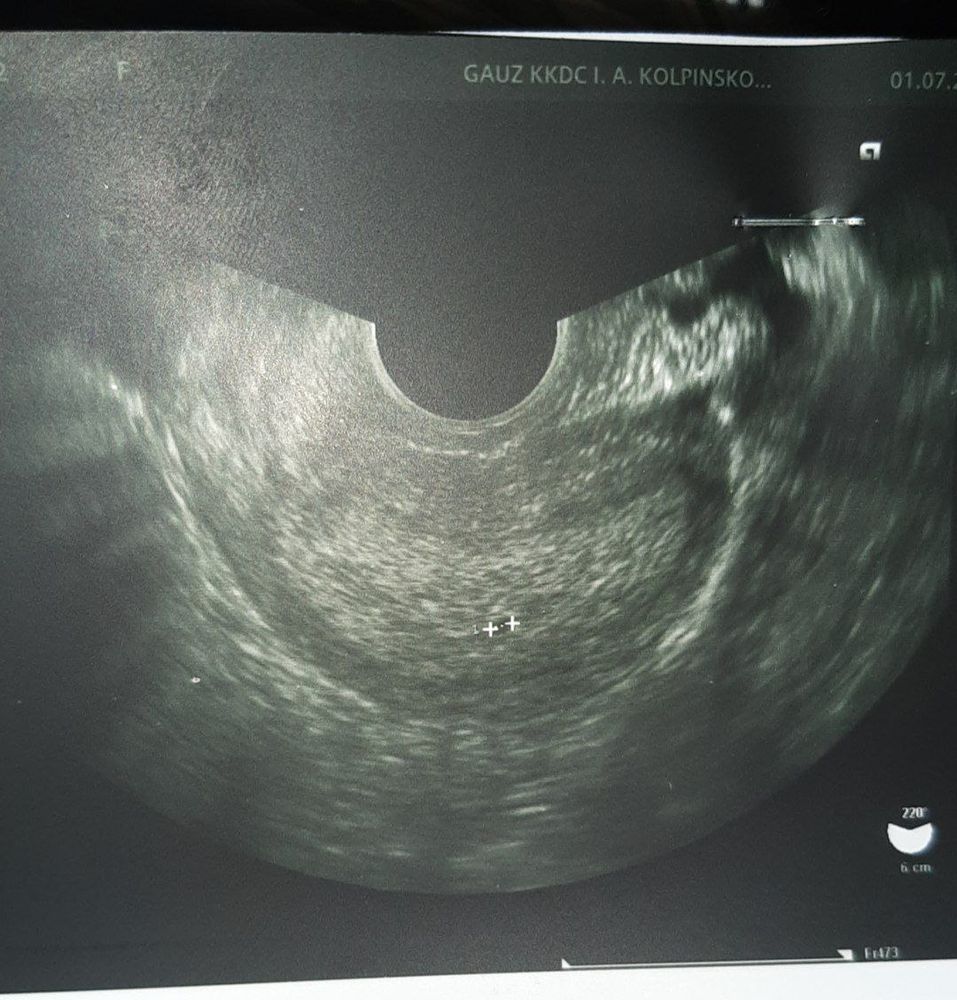

Сделала узи , говорят подозрение на плодное яйцо )

но еще один вопрос.... могут ли на узи увидеть беременность сроком меньше 2х недель ??

Викки , сначала обратилась к гинекологу так как один цикл пропущен был , потом живот стал болеть прям как во время месячных , направили на узи , там сказали что большое подозрение на беременность меньше 4х недель и узи показало овуляцию

Если хгч больше 1000 УЗИ покажет беременность

Беременны,но для узи рано еще наверно,у вас задержка есть?сдайте хгч когда будет больше 1000 идите на узи

Полоска на тесте зависит от уровня хгч,чем он выше,тем полоска ярче, естественно на маленьких сроках с бледной полоски и начинается беременность,а потом она уже становится яркой,на УЗИ видно беременность при хгч от тысячи